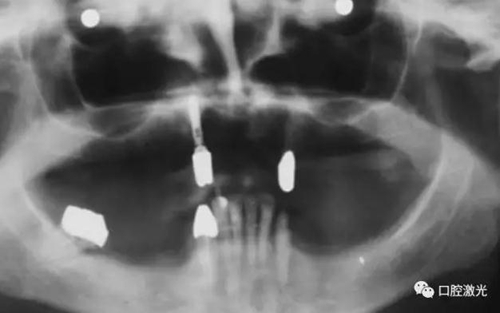

患者女性,43歲。在18年前在13位置上安裝種植體。整個(gè)上顎除23外,牙盡缺失。安裝種植體后,在種植體及23上固定套筒冠義齒。3年后患者發(fā)現(xiàn)刷牙時(shí),臨近13有大量出血現(xiàn)象。通過(guò)探針檢查發(fā)現(xiàn)深度達(dá)6mm。

對(duì)患者實(shí)施局部麻醉,隨后在種植體位置進(jìn)行翻瓣。利用塑料刮治器將肉芽組織清除干凈,并將翻瓣邊緣削薄。此時(shí)在種植體周圍可見(jiàn)明顯骨缺失。

治療6個(gè)月后恢復(fù)情況